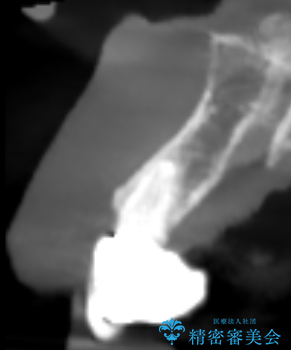

- 歯茎の大きな腫れを主訴に来院された患者様です。前歯5本にはブリッジが装着されていました。レントゲン検査より、右上3番に大きな根尖病巣が認められ、さらに左上1、2番の支台歯にも破折があったため、抜歯を行いました。その後、インプラントを3本埋入し、オールセラミッククラウンのブリッジで補綴しました。

術前のCT画像より、抜歯即時インプラントが可能と判断したため、抜歯と同時にインプラント埋入を行いました。術式にはセミルーナーフラップを用い、唇側の骨吸収を抑える目的でルートメンブレンテクニックを併用しました。